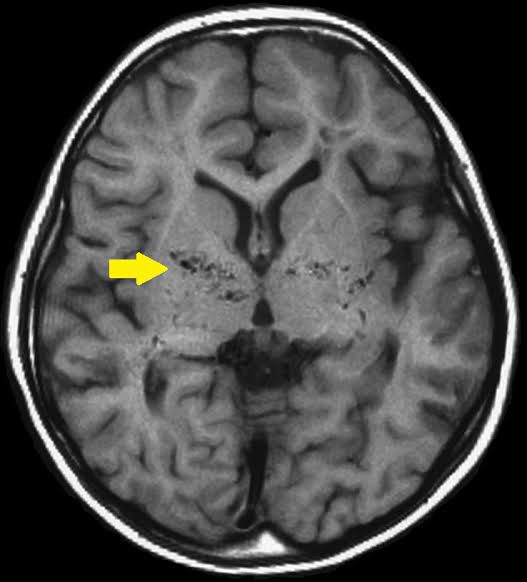

Moyamoya disease is a rare blood vessel (vascular) disorder in which the carotid artery in the skull becomes blocked or narrowed, reducing blood flow to your brain. Tiny blood vessels then develop at the base of the brain in an attempt to supply the brain with blood. The condition may cause a ministroke (transient ischemic attack), stroke or bleeding in the brain. It can also affect how well your brain functions and cause cognitive and developmental delays or disability.